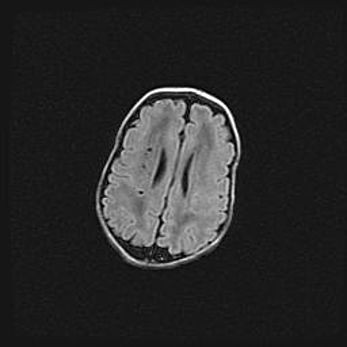

Наружная гидроцефалия с возможной атрофией височных областей.

Возраст: 28 дней

Вес: 3670 г

Пол: мужской

Окружность головы: 38 см

Срок гестации: 40 недель

Гидроцефалия головного мозга у новорожденных – это заболевание, которое характеризуется скоплением избыточного количества спинномозговой жидкости в желудочковой системе головного мозга в результате затруднения её перемещения от места выработки к месту поглощения в кровеносную систему или вследствие нарушения абсорбции. При открытой наружной форме гидроцефалии у новорожденных расширяются и переполняются субарахноидные пространства.

При нормотензивных  формах,  которые,  как  правило,  являются  следствием  перенесенных ишемических  повреждений  паренхимы  мозга,  возможно  сочетание микроцефалии  с нормотензивной гидроцефалией. В основе данных изменений лежит атрофия больших полушарий с преимущественной  локализацией  в  лобно-височных  областях.